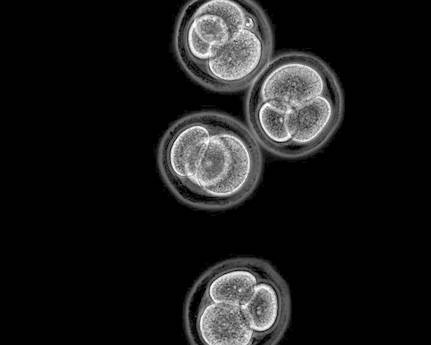

Embrioni di topo allo stadio in cui sono costituiti da 4 cellule (fonte: Kirill Makedonski). Osservando il modo in cui agisce il cocktail di geni, gli autori dello studio hanno scoperto che durante le prime fasi dello sviluppo embrionale le cellule della pelle perdono la loro identità e lentamente ne acquisiscono una nuova, a scelta tra le tre disponibili. Si tratta del primo esperimento di questo tipo ed è un notevole passo avanti rispetto alla procedura messa a punto nel 2006 dal gruppo di Shinya Yamanaka, dell’Università di Kyoto, che prevede l’introduzione di quattro geni. Grazie a quell’esperimento, premiato nel 2012 con il Nobel per la Medicina, è diventato possibile far regredire nello sviluppo una cellula adulta. Tuttavia il viaggio nel tempo di quelle cellule non arrivava così indietro fino a ottenere i tessuti che si formano all’inizio dello sviluppo embrionale.